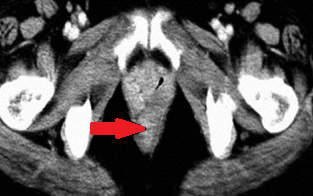

Red arrows – Rectal stromal tumor. Multiple liver metastases (Courtesy Dr. V. Penopoulos)